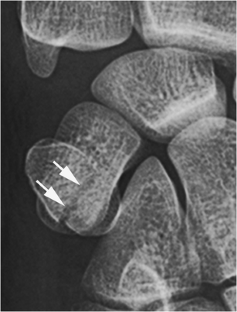

Fig. 3